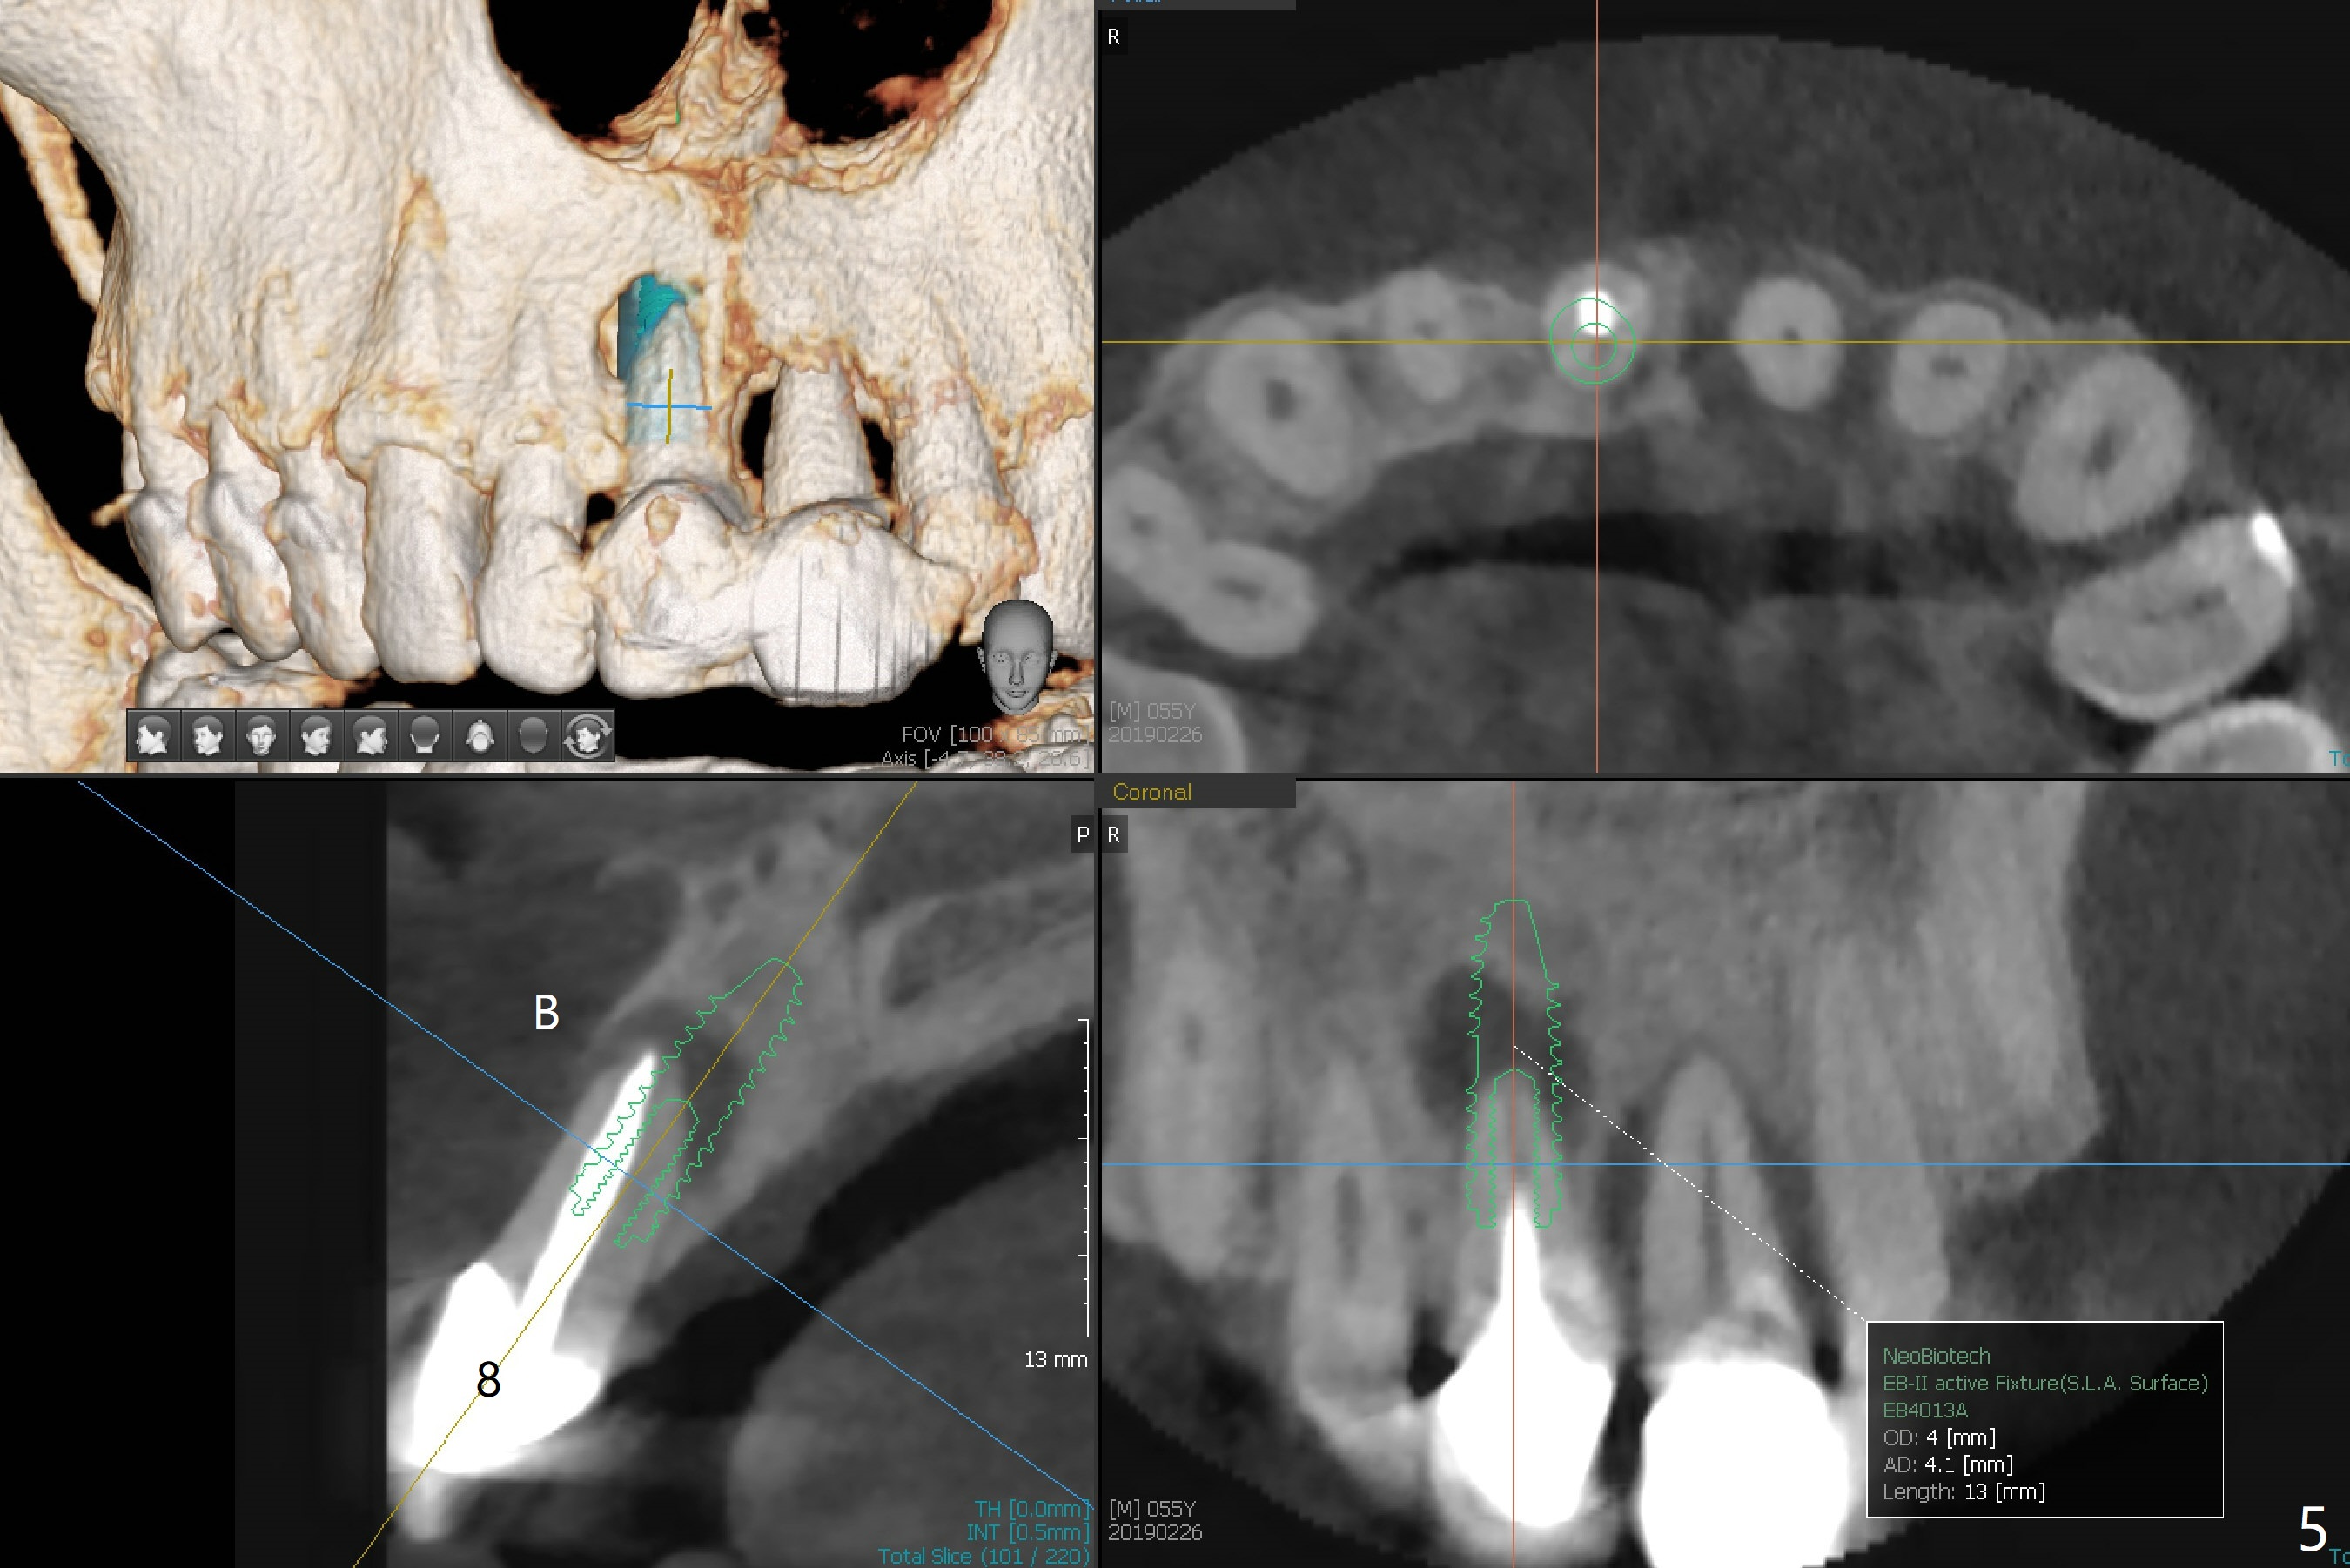

A 55-year-old man does not like the extruding tooth #9 (Fig.1,2). While there are fistulae associated with the two central incisors (arrowheads in Fig.1,2), bone loss appears to be apical at #8 and crestal at #9 (Fig.3 *). To avoid iatrogenic bone loss associated with two neighboring implants in the cosmetic zone, apicoectomy is to be performed at #8, while an immediate implant will be placed at #9 with guide at the same time (Fig.4). Furthermore there is missing or thin buccal plate at #8 (Fig.5 B).